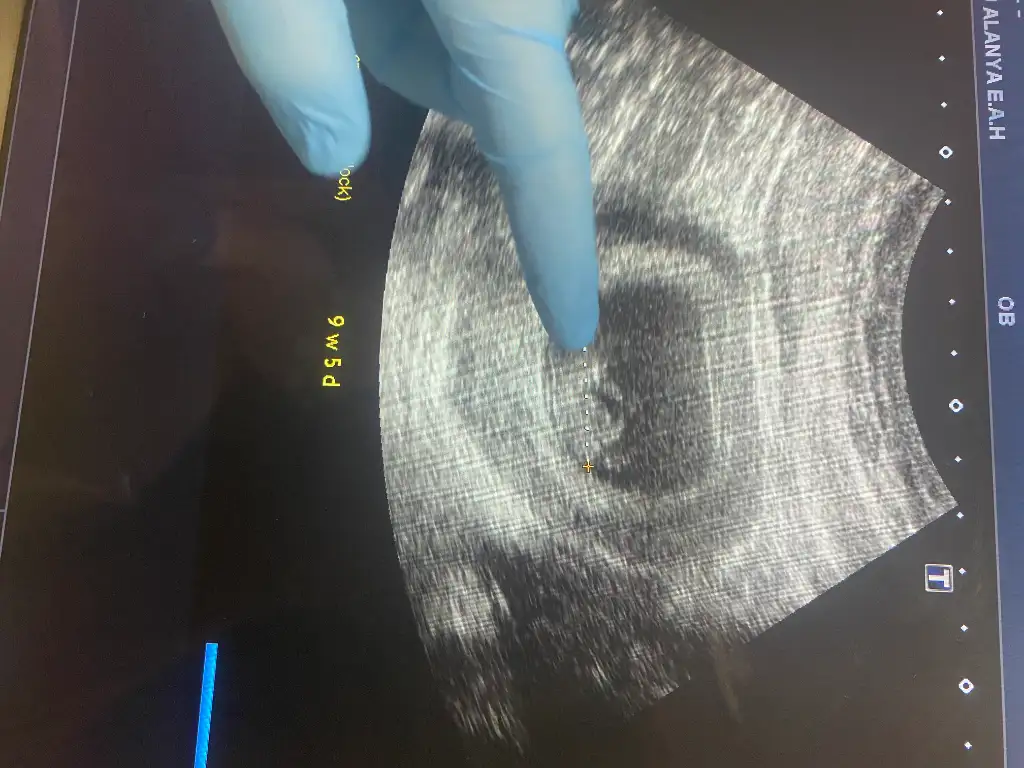

Ay benim için erken haftaya tekrar gideceğiz ama tahmin var mı atayım

Eklentiler

• IMG_6085.webp

45,8 KB · Görüntüleme: 22

• IMG_6090.webp

23,4 KB · Görüntüleme: 24